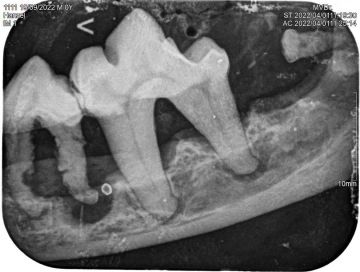

Diagnostics - intraoral X-ray

The x-ray of your pet's teeth is similar to that of humans. An x-ray machine using a small amount of radiation is used to view the inside of your dog's teeth and those areas below the gum line that are hidden. Unlike humans, animals must be under general anesthesia for a dental X-ray, as it is practically impossible to get them to hold the plate in their mouth and not bite into it. You can read more about the anesthesia itself and what it all entails here.

Animals just can't tell us when their teeth are sick and some never show that they are in pain. In many cases, an intraoral x-ray is the only way we can tell that your pet has a serious dental problem that can be treated and the discomfort alleviated.

It should be noted that quality dental treatment requires x-rays of the teeth. Without an x-ray of the teeth, it is practically impossible to assess the condition of the periodontium, and diseases that occur below the level of the gums are invisible to the human eye.